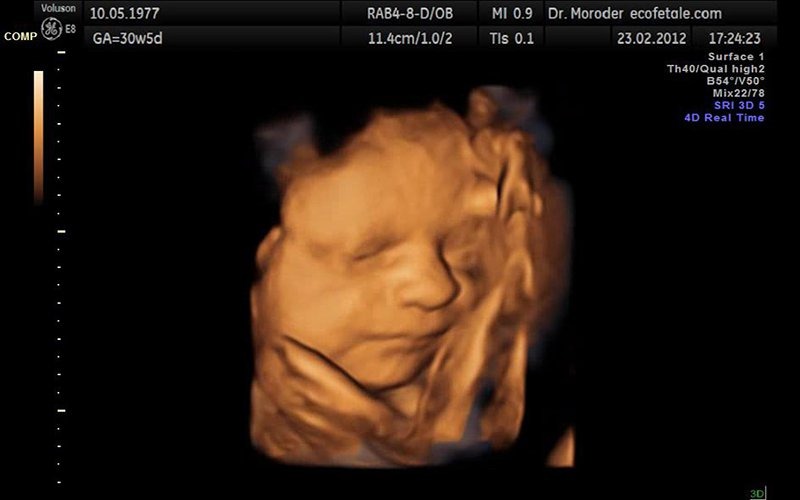

Thai nhi tuần 21 đã đạt kích thước khoảng 28 cm và nặng khoảng 450 gram. Mặc dù vẫn còn nhỏ, nhưng bé đã bắt đầu có hình dạng của một trẻ sơ sinh với các bộ phận trên gương mặt như môi, mắt và lông mày trở nên rõ nét. Chồi răng nhỏ cũng đang hình thành dưới lợi. Dù mắt chưa mở hoàn toàn, bé có thể cảm nhận được ánh sáng và bóng tối, đồng thời có những phản ứng rõ rệt với chúng. Hệ thần kinh đang phát triển, và nhịp tim cũng bắt đầu ổn định.

Ngoài ra, thai nhi được bao bọc bởi một chất màu trắng giống mỡ gọi là chất gây, giúp bé an toàn và di chuyển trong nước ối. Thông thường, chất này vẫn còn dính trên da bé sau khi sinh. Vào tuần 21, bé bắt đầu hoạt động mạnh mẽ với những cú đạp rõ rệt và di chuyển linh hoạt trong bọc nước ối. Bé cũng đã có khả năng nhận biết âm thanh bên ngoài nhờ sự phát triển của xương tai. Mẹ bầu cần chú ý đến cảm xúc của mình, vì chúng có thể được bé cảm nhận và ảnh hưởng đến tâm trạng của bé.